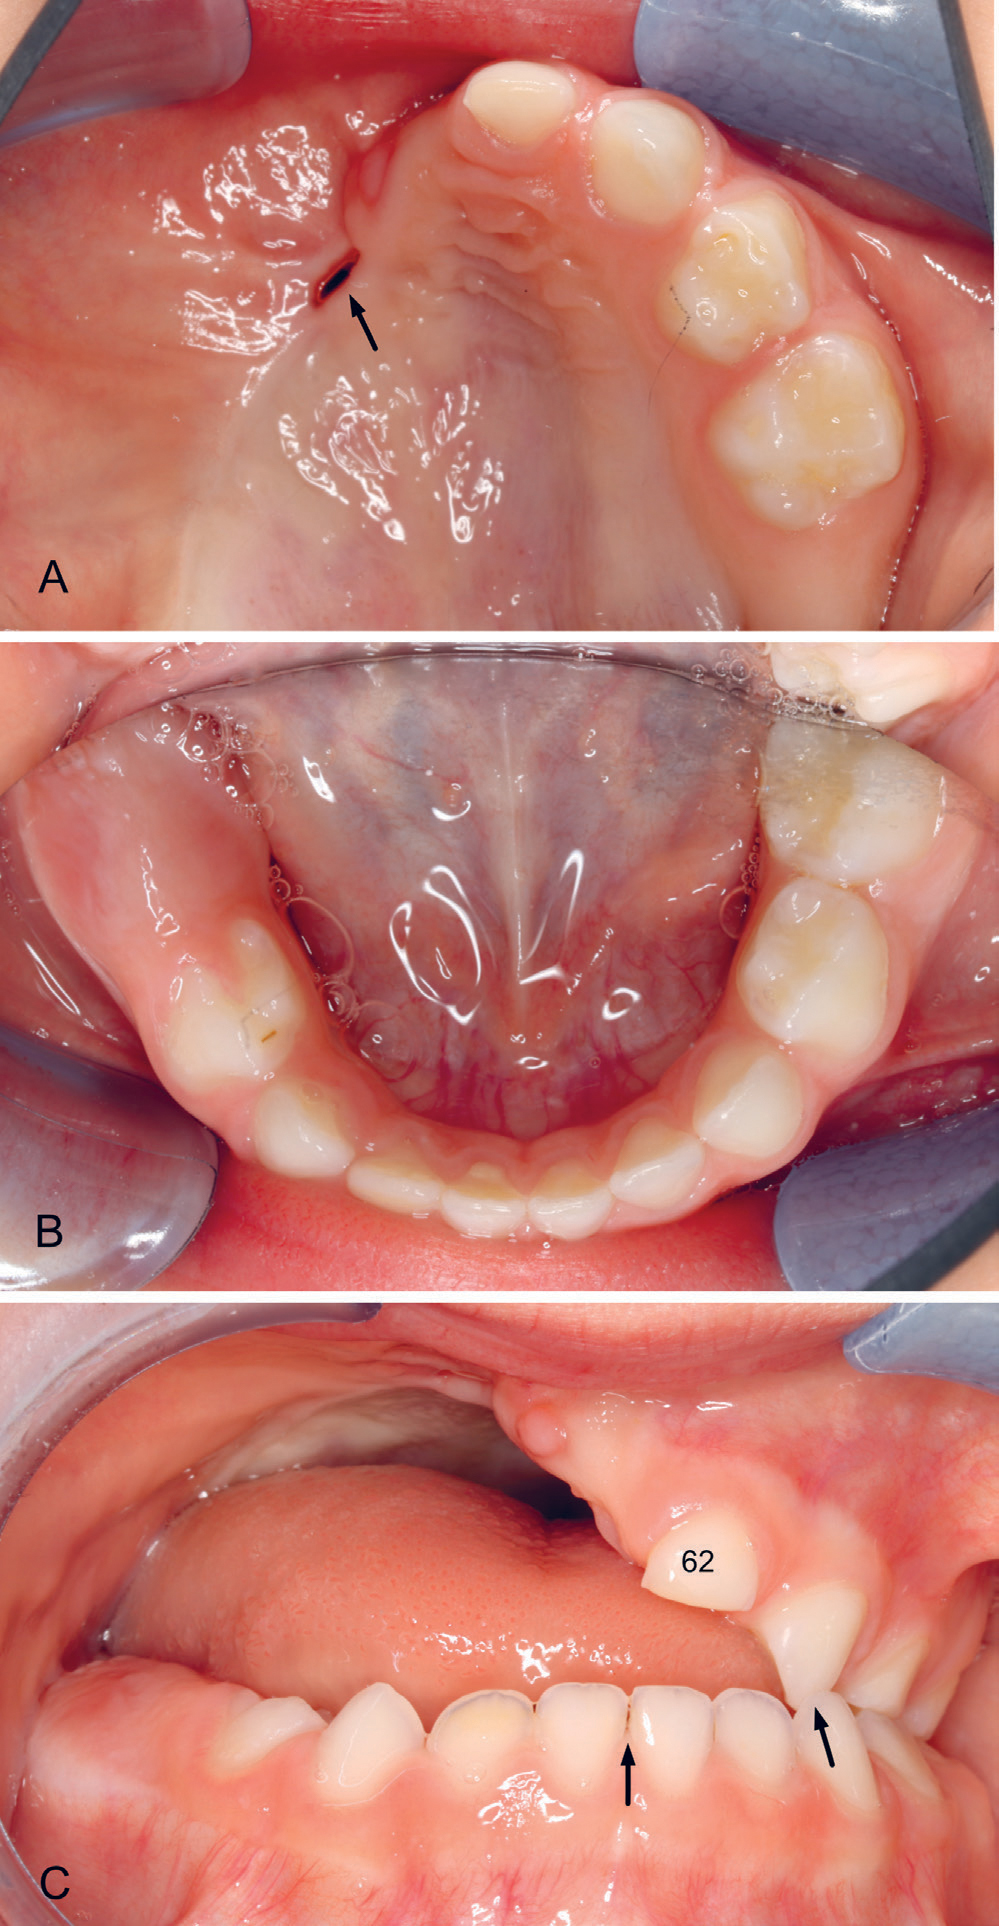

Oral helse er viktig for generell helse, ernæringsstatus og livskvalitet, og hører med i en helhetlig omsorg for barn under behandling for kreft. Tanndannelse er en komplisert prosess som involverer en rekke signalmolekyler, interaksjon mellom vevstyper og dannelse av spesialiserte celler (24). Perioden fra 0–6 år er den viktigste perioden for utvikling av det permanente tannsettet (25). Vekst av ansiktsskjelettet og kjevene er også mest intens i denne perioden samt i puberteten og samsvarer med periodene der insidensen av barnekreft er høyest (1). Kirurgi i hode hals området og de toksiske effektene av kreftbehandling i disse aldrene kan derfor forårsake uopprettelige skader på utvikling av ansikt, kjever og tenner (figur 1 A-C).

Figur 1. A–C. Bilder fra en 3 år gammel jente etter behandling av tumor i høyre overkjeve. Ved 3–5 måneders alder ble høyre halvdel av maxilla fjernet kirurgisk (hemimaxillectomi) etterfulgt av kjemoterapi. A: Gjenstående tenner i venstre overkjeve, tann 62, 63, 64 og 65 og fistel anteriort i ganen i operasjonsarret (pil). B: I underkjeven er det forsinket erupsjon høyre side av tennene 84 og 85. C: Okklusjonen: Åpent bitt også anteriort ved tann 62, kryssbitt av tennene 63/73 (pil) og markert midtlinjeavvik (pil). Hun har ingen sugeuvaner.